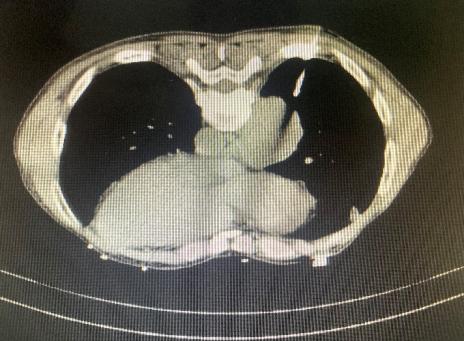

CT引导下肺肿物穿刺活检

CT引导下肺肿物消融治疗